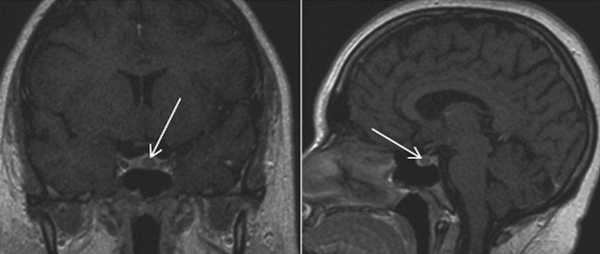

МРТ гипофиза в норме

МРТ гипофиза с контрастом. После введения контрастного вещества в гипофизе происходит его накопления и он выглядит светлым. Только участок опухоли не накапливает контрастное вещество и выглятит темным (стрелка).